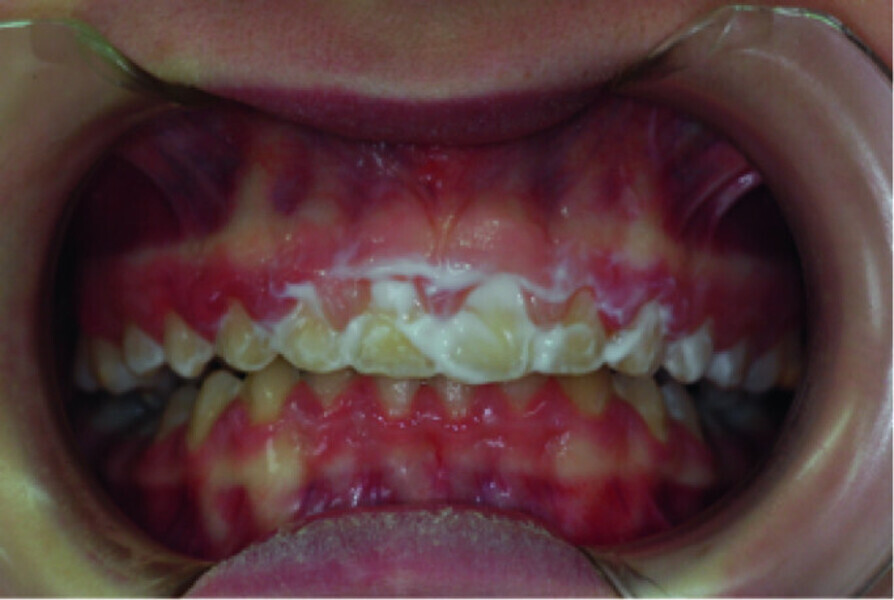

Use of diode laser in the treatment of gingival enlargement during orthodontic treatment